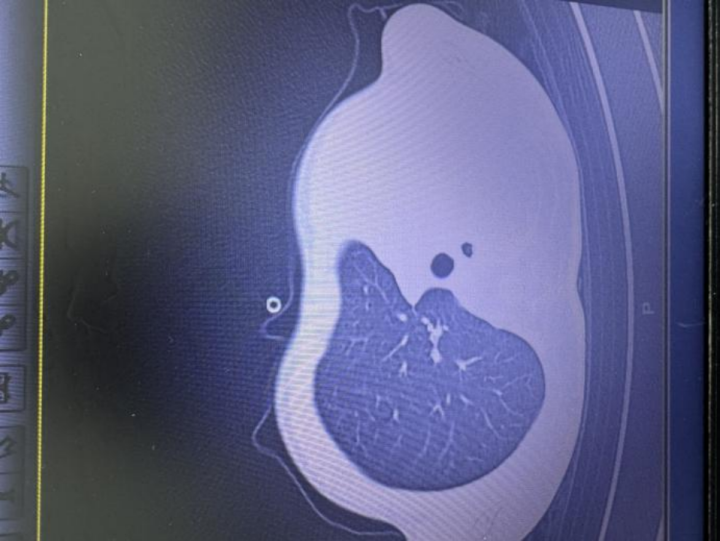

急诊检查结果让医护人员瞬间紧张:验血显示炎症指标大幅上升,胸片发现左侧肺叶几乎不工作了,影像学中变成大片白色,即通常所说的“白肺”,意味着肺功能严重受损,孩子已经缺氧,随时有窒息危险。

图:影像显示肺白了一半